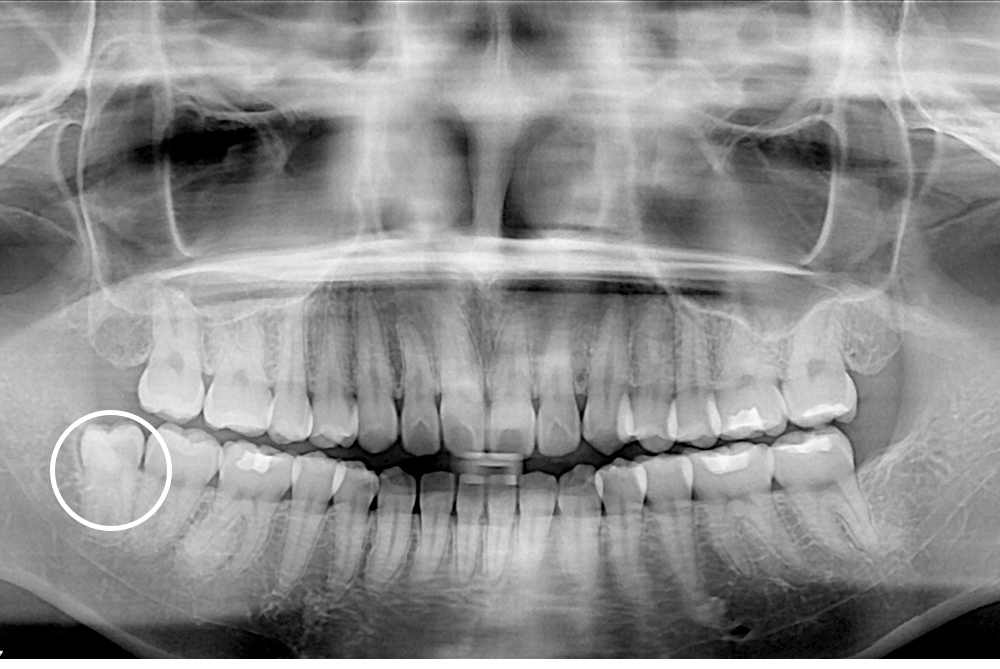

[사랑니] 매복 사랑니 발치

치료후 : 2016-03-28

세종치과는 구강악안면외과학 박사이신 원장님이 발치하는 치과입니다.